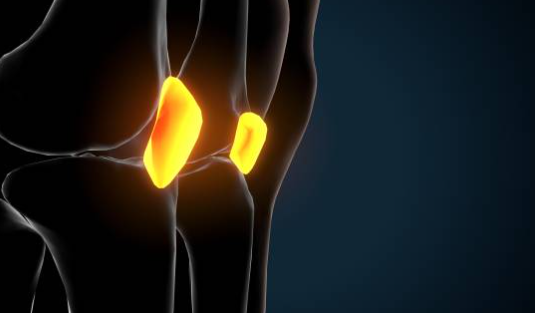

무릎 안쪽 통증 원인 대표적인 9가지와 셀프 마사지 방법에 대해서 알아보겠습니다.무릎은 우리 몸의 중요한 관절 중 하나로, 걷기, 뛰기, 앉기 등 다양한 움직임에 참여합니다. 하지만 무릎에 과도한 부담이 가해지거나 외부 충격이 가해지면 무릎 안쪽에 통증이 발생할 수 있습니다.

무릎 안쪽 통증은 단순한 근육통일 수도 있지만, 심각한 질환의 증상일 수도 있으므로 주의해야 합니다. 무릎 안쪽 통증은 무릎 관절이나 인대, 연골, 근육 등의 손상이나 염증 때문에 발생할 수 있습니다. 무릎 안쪽 통증의 원인은 다양하지만, 대표적으로 9가지를 알아보겠습니다.